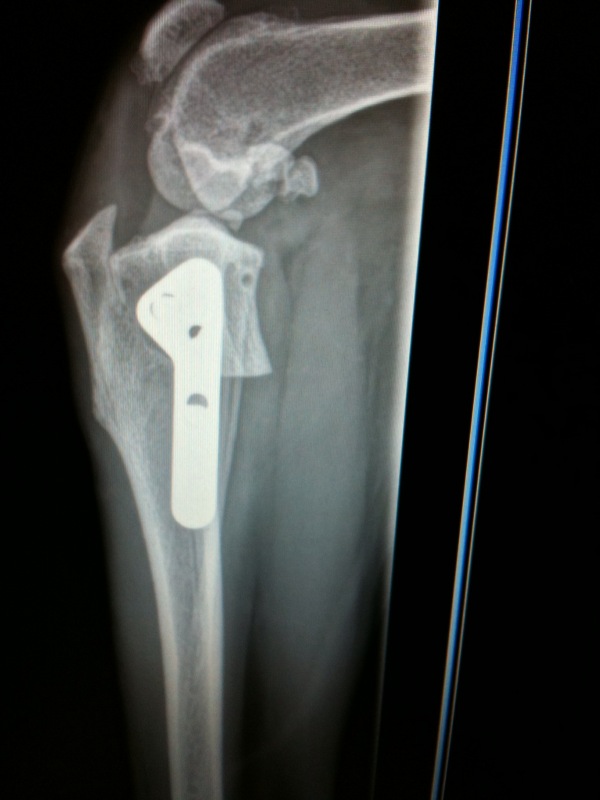

From www.researchgate.net

FIGURE E Comparison of TPLO radiographs (A) Immediately postoperative... Download Scientific Tplo Surgery Gone Wrong a tibial plateau leveling osteotomy (tplo) is one of several potential surgical procedures to repair a torn acl in. discover the essentials of tplo surgery for dogs, including how often complications occur, risk factors, and tips for ensuring a successful outcome. the signs of tplo failure and complications in dogs is something you may be wondering about. Tplo Surgery Gone Wrong.